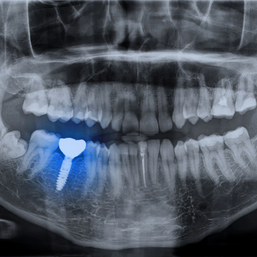

We understand the concerned of pain and discomfort associated with trips to the dentist. Larger dental procedures like Dental Implants can cause a large amount of anxiety but do not worry, the placement of Dental Implants is not typically painful. The actual placement of Dental Implants on itself tends to be less bothersome than having teeth extracted. We also do several things to reduce any post-op inflammation and discomfort, this includes the use of several pre and post-op medications that helps to reduce the risk of pain swelling and infection.

During the actual procedure, you will be completely numb and then for comfort and ease of mind, we offer sedation a pair of headphones to help you relax even more during the procedure.

You would be surprised to know how many people end up falling asleep during the middle of the procedure with this. If you believe your anxiety will still not be quelled, we can arrange to have you be put to sleep with a specialist to have the surgical procedure done. Once the implants are placed, you can’t even tell that they are in the bone other than a little smooth healing hump that maybe barely sticking out from the gums.